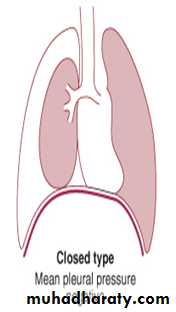

2-Closed pneumothorax; Communication between the lung and pleural space seals off as the lung deflates and does not reopen the mean pleural pressure remains negative spontaneous reabsorption of air and re-expansion of the lung occur over a few days or weeks, and infection is uncommon.